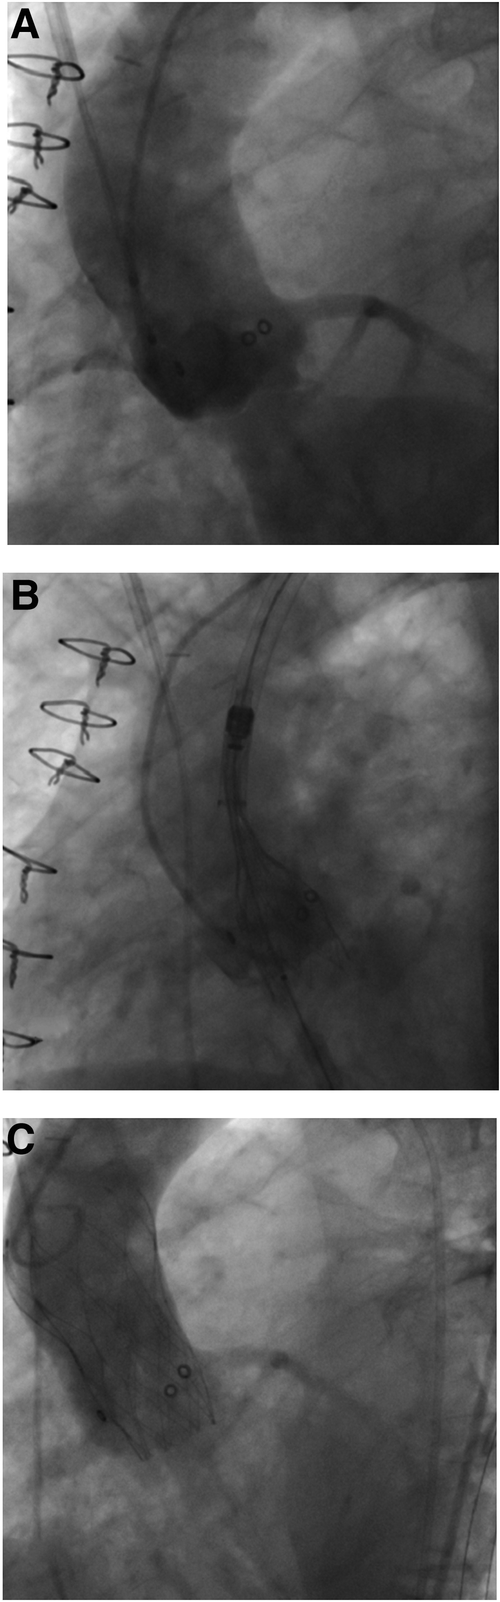

Figure 3

Valve-in-valve procedure using a self-expanding intra-annular transcatheter heart valve for treatment of a failing porcine surgical bioprosthesis. (A) Failing 23 mm (True ID: 19 mm) Mosaic surgical bioprosthesis with severe valvular regurgitation. (B) Placement of a 23 mm self-expanding intra-annular transcatheter heart valve into the surgical bioprosthesis and alignment of both lower stent parts. (C) Final position with absence of any paravalvular leakage.